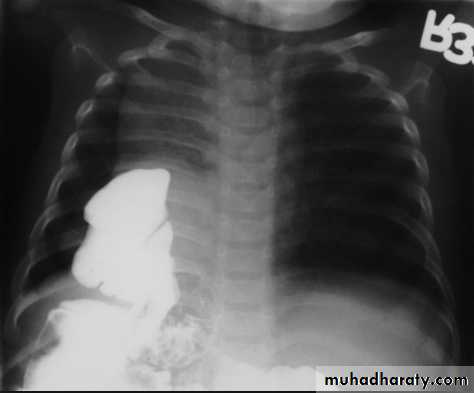

• A mediastinal mass due to a hiatus hernia is usually easy to diagnose on plain films because it often contains air and may have a fluid level, best seen on the lateral view

Large hiatus hernia, seen with fluid in stomach